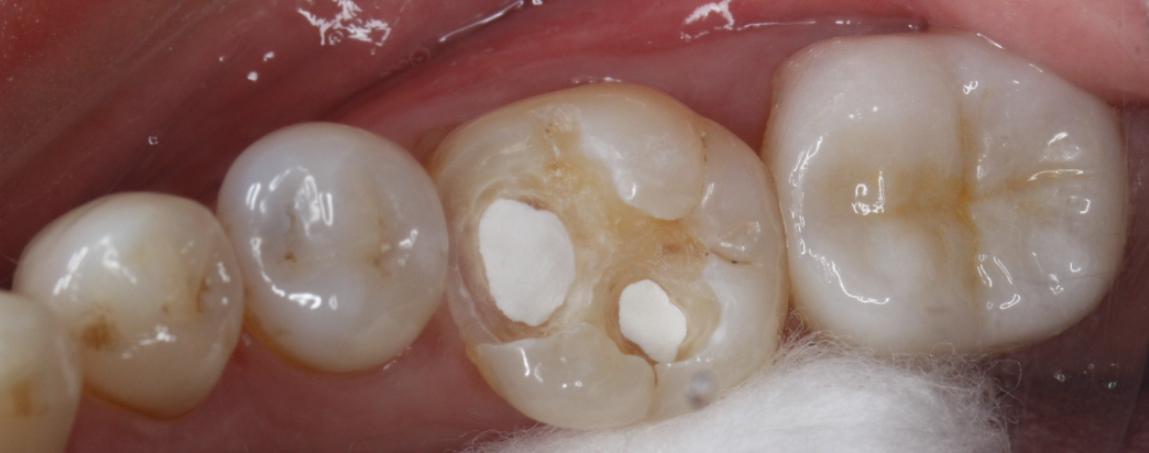

嵌体修复是一种精准的修复方式,特别适合像患者这样龋坏较深但无需根管治疗的情况。该患者选择了西诺德全瓷嵌体修复,去龋坏,IROOT-BP间接盖髓+光固化玻璃离子+3M流动树脂垫底。基牙预备,排龈,精修,然后CEREC扫描,获取牙齿模型,定制出与缺损部位完全匹配的陶瓷嵌体。嵌体制作完成后,医生将其粘接固定在牙齿上,恢复了牙齿的形态和功能。